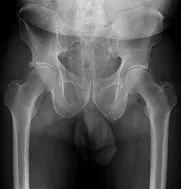

Practice Orthopedics online MCQs and assess your clinical knowledge. High-yield questions for medical students and orthopedic residents.